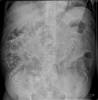

Diverticulosis de colon.

Diverticulosis de colon. Megacolon.